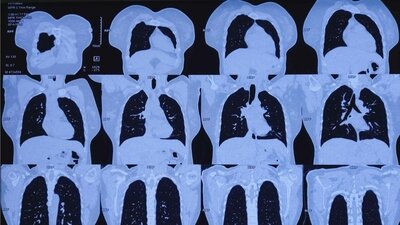

Früherkennung von Lungenkrebs kommt auch für Raucher

In Deutschland soll die Früherkennung von Lungenkrebs bei Rauchern starten – noch sind Fragen offen. zum Artikel